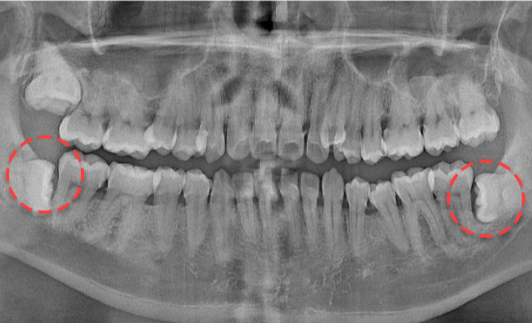

양쪽 하악 매복 사랑니 발치 Before X-Ray

치료시작일

2019.11.05

AFTER

양쪽 하악 매복 사랑니 발치 After X-Ray

치료종료일

2020.12.24

양쪽 하악 매복 사랑니 발치